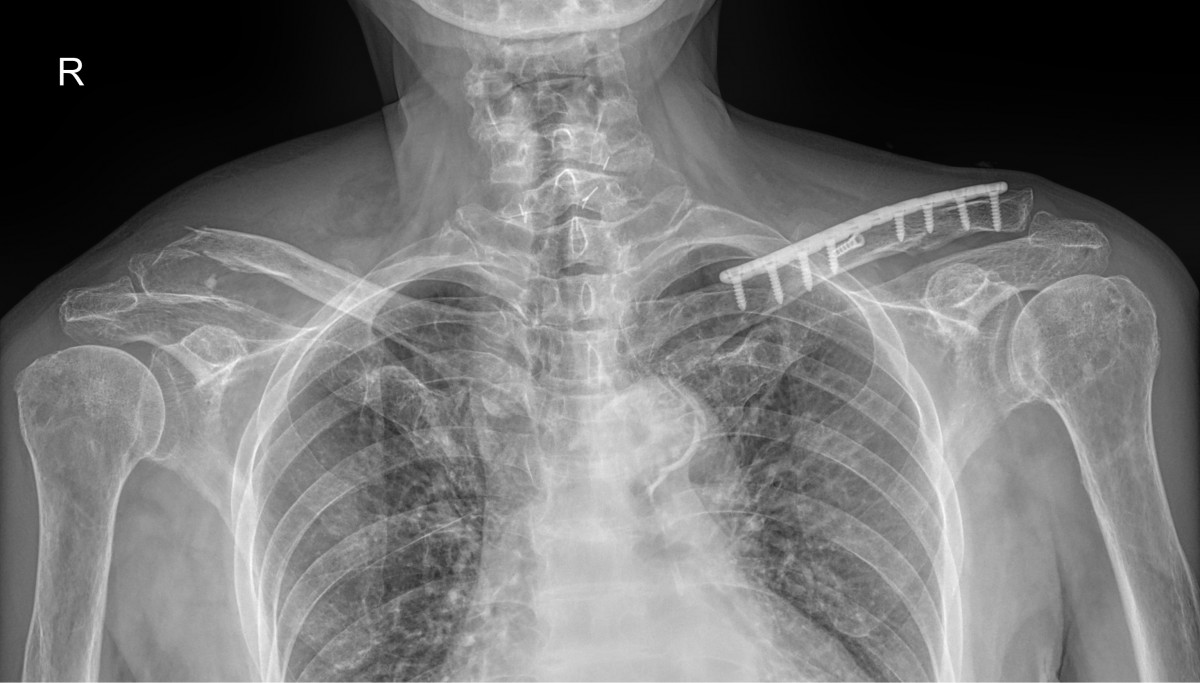

정지영원장님 어깨 골절 수술 장매O 환자

작성자 최고관리자 댓글 0건 조회 709회 작성일 25-09-16 16:40

dae765e4d9ac96aee867c9d6292d8784_1758008392_6955.jpg